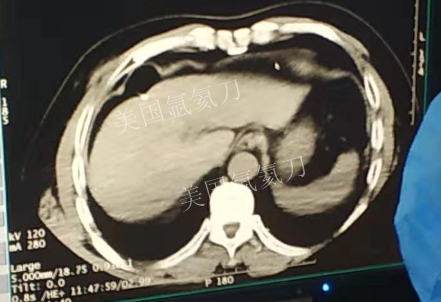

59岁男性肝部氩氦刀手术治疗

发布人:美国氩氦刀技术官方网站    发布时间:2019/3/13 15:42:57